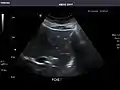

- Pancreas

Pancreas: Visualized portions unremarkable.